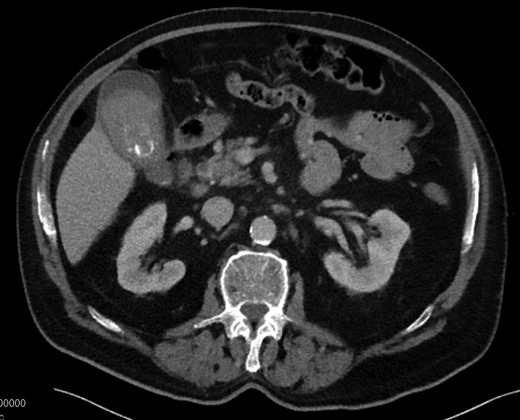

Laboratory results were as follows: white blood cell count 10.5, hemoglobin 13.9, platelet count 164, Total bilirubin 3.8, AST 133, ALT 200, alkaline phosphatase 339, lipase 33, protime 36.3, INR 4.2. Abdominal ultrasound was obtained to evaluate for potential gallbladder/biliary pathology given his presentation. The ultrasound demonstrated gallstones with findings concerning for chronic cholecystitis with a common bile duct measurement of 8 mm. To further evaluate the cause for the patient’s abdominal pain, a computed tomography (CT) scan was performed of the abdomen and pelvis. CT findings demonstrated an abnormal gallbladder with stones and dense intraluminal debris measuring 53 Hounsfield units. Similar debris was seen in the common bile duct with a measurement of 17 Hounsfield units. Active contrast extravasation into gallbladder lumen was not seen on the CT, but Hounsfield units were consistent with intraluminal blood. The common bile duct was measured at 8 mm in diameter without intrahepatic ductal dilatation (Fig. 1).

CT with dense heterogeneous gallbladder contents and cholelithiasis.